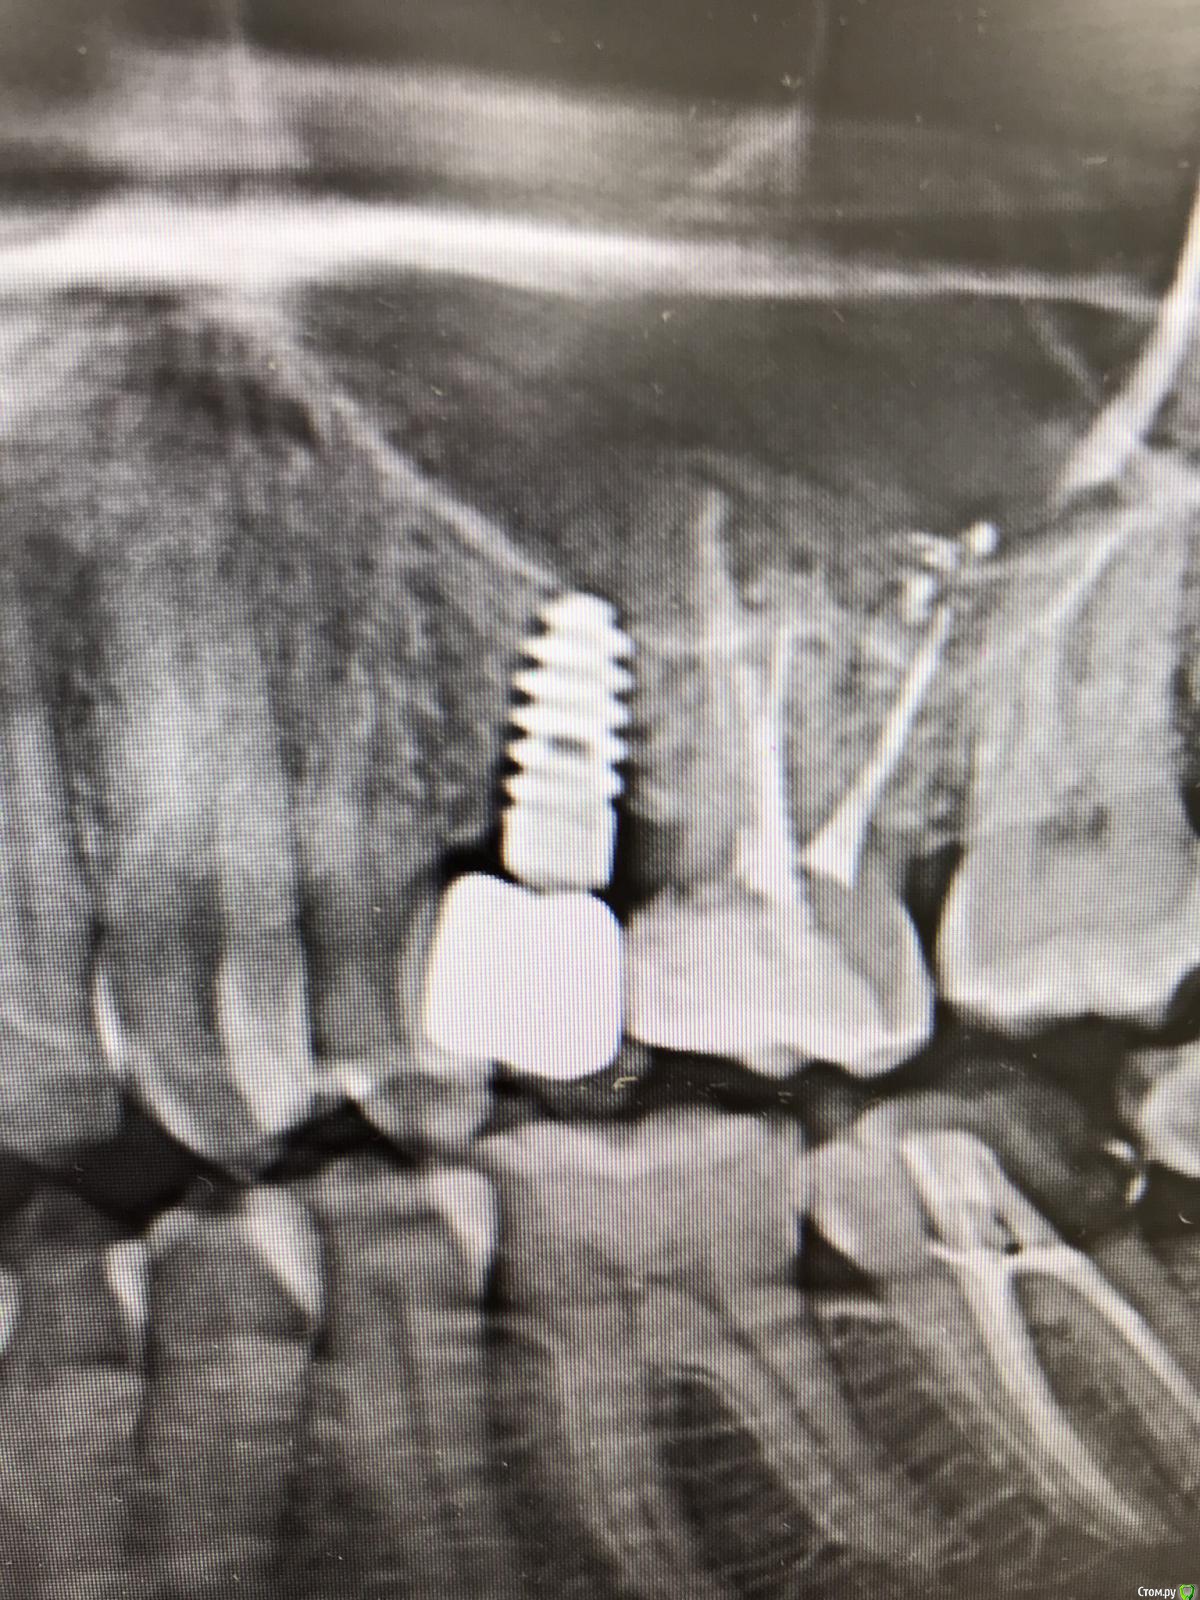

anvladd Опубликовано 24 сентября, 2018 Поделиться Опубликовано 24 сентября, 2018 (изменено) Коллеги подскажите какие отвертки походят под них ? Или абатмент винт единое целое ? Изменено 24 сентября, 2018 пользователем anvladd Ссылка на комментарий

gum Опубликовано 1 октября, 2018 Поделиться Опубликовано 1 октября, 2018 Нужна ли вам отвертка? Судя по снимку имплантат на удаление. 1 2 Ссылка на комментарий

Nazim_NV86 Опубликовано 4 октября, 2018 Поделиться Опубликовано 4 октября, 2018 (изменено) Нужна ли вам отвертка? Судя по снимку имплантат на удаление. Согласен. Слишком апикально. Скорее всего абатмент перекрыт коронкой полностью. Похож на оралтроникс. Изменено 4 октября, 2018 пользователем Nazim_NV86 Ссылка на комментарий

red_butler Опубликовано 5 октября, 2018 Поделиться Опубликовано 5 октября, 2018 Похож на оралтроникс. точно Ссылка на комментарий

АнтонТЛТ Опубликовано 6 октября, 2018 Поделиться Опубликовано 6 октября, 2018 Если это самарские имплантаты СтаС (стоматологическая ассоциация Самары), то там цельные абатменты и фрезерованная поверхность всего имплантата.Лучше сделать прицельный снимок и посмотреть отдельный там винт или нет. Ссылка на комментарий